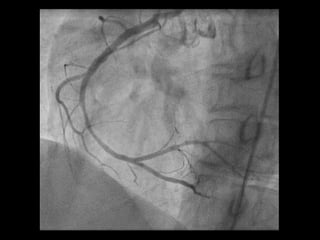

• #63 Ösophagus-Monokontrast mit wasserlöslichem Kontrastmittel (100 ml Peritrast®). Kontrastmittelaustritt im distalen Ösophagus links dorsolateral in die Pleurahöhle ( Pfeil )